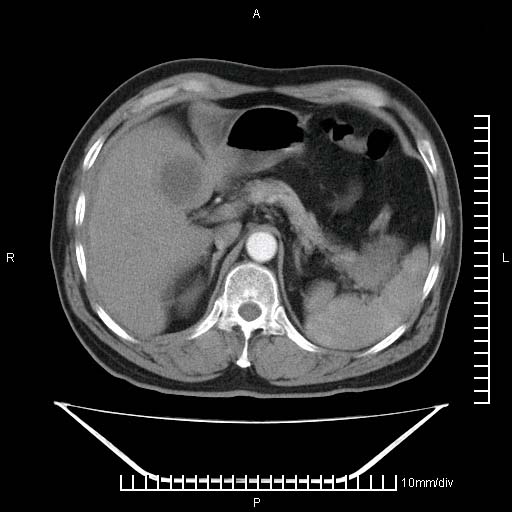

标题: CT25082:肝脏增强:男性,70岁 [打印本页]

标题: CT25082:肝脏增强:男性,70岁

患者以心脏疾病收住院,腹部无明显症状,b超查肝脏有占位。

增强效果不理想。考虑转移,胆囊壁明显增厚,不排除胆囊癌肝转移。

牛眼征,中心坏死无强化,外缘强化,最外缘又见低密度,考虑转移,与脓肿鉴别

肝内多发转移瘤,右下肺炎症并少量胸水。胃壁增厚建议胃镜,胰尾部“病变”为肠管。

1)肝脏多发性转移瘤(不排除胰尾癌转移所致可能)。2)腹水。3)右侧少量胸腔积液。

ct25082 结果:转移瘤

外院mr结果:胰尾恶性占位。

肝多发低密度灶;轻度强化,较水密度高,考虑转移,不排除肝脓肿